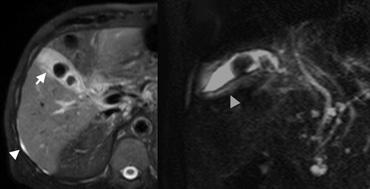

Ở cùng bệnh nhân viêm gan do thuốc, MRI được thực hiện để đánh giá đường mật do kết quả xét nghiệm chức năng gan bất thường.

Ở ngoài cùng bên trái, hình ảnh MRI chuỗi xung T2W SPIR theo mặt phẳng axial (A) cho thấy một lượng nhỏ dịch cổ trướng (đầu mũi tên), gợi ý rằng dày thành túi mật (mũi tên) có thể do nguyên nhân toàn thân ngoại sinh.

Kế bên là hình ảnh HASTE chếch để chụp MR đường mật, loại trừ sỏi ống mật chủ.

Dày thành túi mật (đầu mũi tên) cũng được thể hiện rõ.